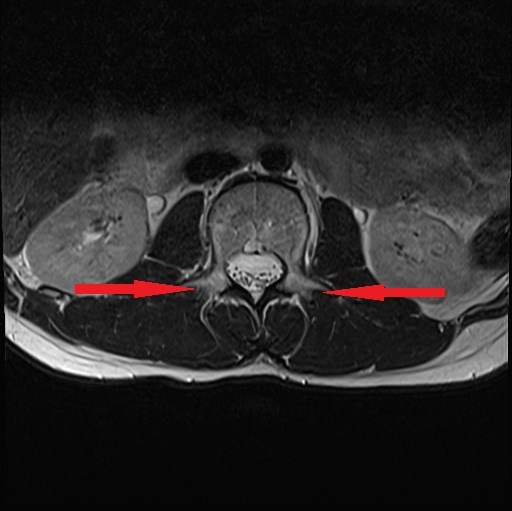

4月 MRI検査にて腰椎分離症の診断。コルセット装着の保存療法にて安静加療の指示。

6月 再検査。腰椎分離症の進行が見られた。

9月 再検査。変化なし。ボルトで脊椎を固定する手術(脊椎固定術)を打診される。

10月15日 再検査にて分離部位の癒合が認められるとの所見。

11月15日 再検査にて更に分離部位の癒合が認められるとの所見。現時点で腰痛や下肢疼痛など症状の再発は無し。

今回ご紹介する症例は、半年もの間一向に改善しなかった腰椎分離症がわずか1ケ月半の間に、しかも4回の施術で劇的な改善が見受けられたことについて、病院での一連の検査が終了した後に受療者の保護者より病院での検査記録の提供を受け、発症から治癒に至るまでの詳細について時系列でお伝えするものす。また、この症例はこれらの画像提供を受ける2ヶ月前の段階で既に筋肉反射テストにより損傷部位を正確に特定し、骨の癒合を促す施術を行った結果です。この目まぐるしい回復に専門医も只々驚愕しきりだったとか。本人は手術を受けるつもりでいたようですが、我が子の体にメスを入れることを良しとしなかった母親の慈愛が正しい選択に向かったのでしょう。CTやMRIは最先端の医療検査と思われがちですが、残念ながら損傷が分ったとしてもそこには回復させる術はありません。正しい検査のみが治癒の道筋を着けることを可能とします。体は常に自力で治ろうとして様々な症状を発現しています。体の訴えに耳を傾ける時、きっと自身の治癒力が成せる奇跡のような回復劇が待っていることでしょう。当院の施術には何のリスクもありません。手術を受ける前に是非ご相談ください。